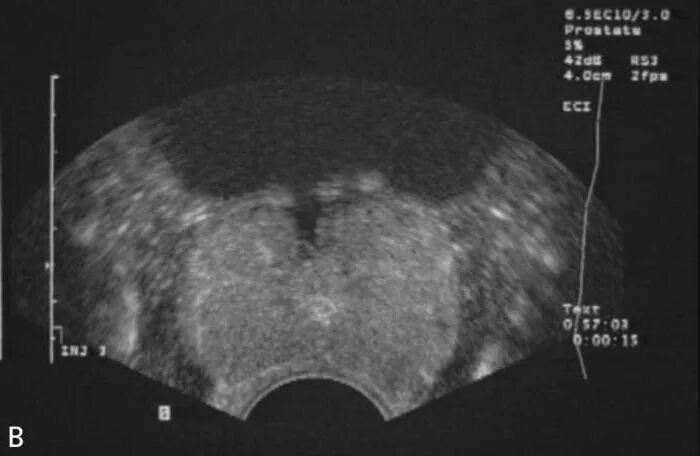

Бактериальная простата